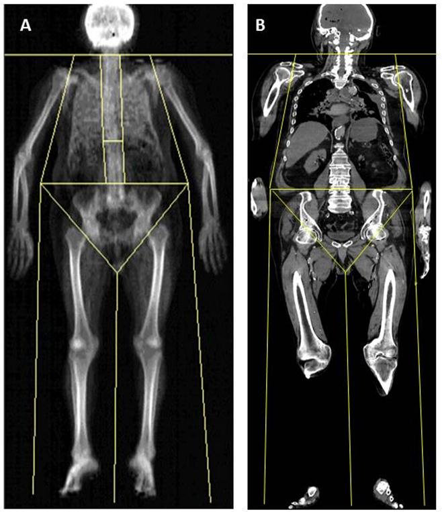

Chụp cắt lớp vi tính tầm soát toàn thân là một kỹ thuật vô cùng quan trọng trong chẩn đoán cận lâm sàng đặc biệt về ý nghĩa tầm soát di căn hay trong đa chấn thương. Kỹ thuật có thể đánh giá được toàn diện hệ thống phần mềm, xương, xoang…